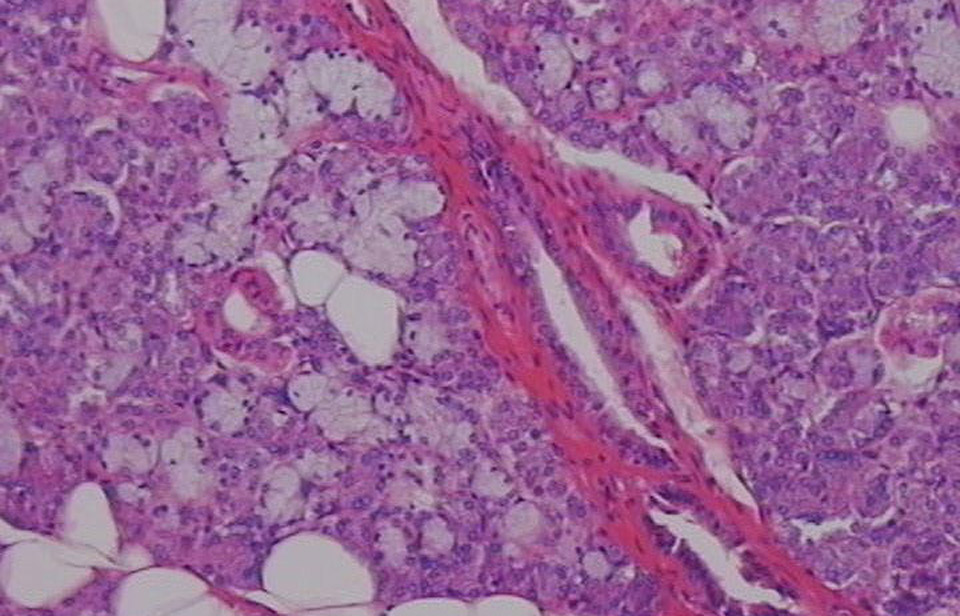

Oι ερευνητές του ερευνητικού κέντρου RIKEN και του Πανεπιστημίου Σόγουα, που έκαναν τη σχετική δημοσίευση στο περιοδικό «Nature Communications», χρησιμοποίησαν ένα 'κοκτέιλ' χημικών ουσιών για να «χειραγωγήσουν» εμβρυικά βλαστικά κύτταρα, ώστε να δημιουργήσουν το στοματικό εξώδερμα από το οποίο αναπτύσσονται οι σιελογόνοι αδένες.

Στη συνέχεια, οι επιστήμονες μεταμόσχευσαν αυτό το εργαστηριακό οργανοειδές του σιελογόνου αδένα στα πειραματόζωα, μαζί με μεσεγχυματικό ιστό, έναν άλλο εμβρυικό ιστό, ο οποίος δημιουργεί τον συνδετικό ιστό ανάμεσα στους σιελογόνους αδένες και στους άλλους ιστούς όπως ο νευρικός.